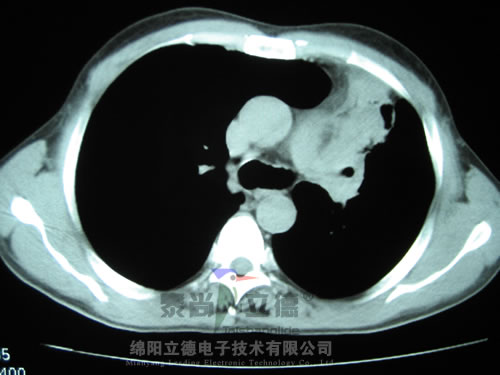

1.jpg

晚期肺癌RF治療中